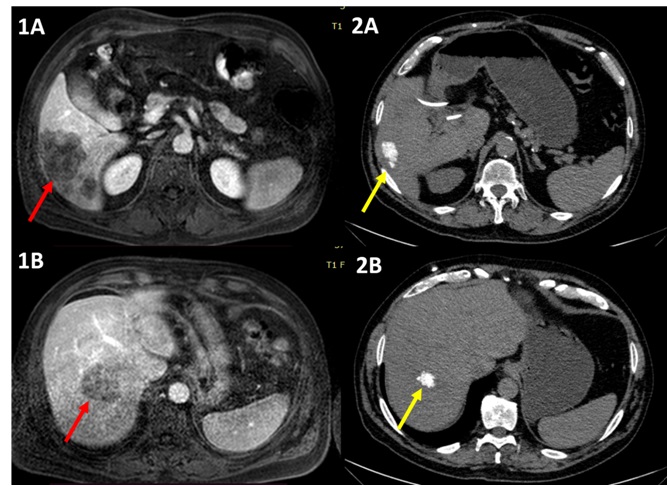

Одним з підходів, що поєднує здатність хіміотерапевтичних препаратів вбивати пухлинні клітини, та місцеве підведення цих препаратів прямо до «точки призначення» через живлячу судину, є внутрішньоартеріальна хіміотерапія печінкових метастазів.

Ця методика передбачає хірургічне встановлення катетера в печінкову артерію та подальше введення через нього хіміотерапевтичних препаратів. Методика широко використовується у багатьох провідних онкологічних центрів світу, зокрема США – Клініки Мейо та Онкологічного центру MD Anderson